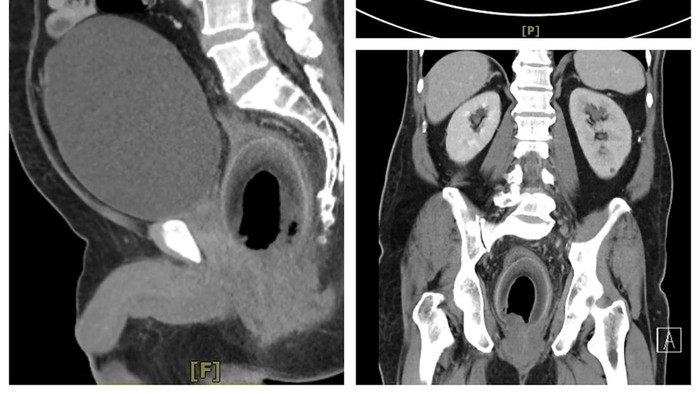

Setelah mendengar keluhan dari pasien, dokter pun melakukan beberapa tindakan awal seperti CT scan. Hasilnya menunjukkan buah kelapa tersebut tersangkut di rektumnya, menekan uretra dan mencegahnya untuk bisa kencing.

Kelapa berukuran panjang 9 cm tersebut kemudian diambil melalui laparotomi, sebuah operasi yang melibatkan pembukaan perut. Petugas medis tidak mengungkapkan kapan pria itu diperbolehkan pulang.